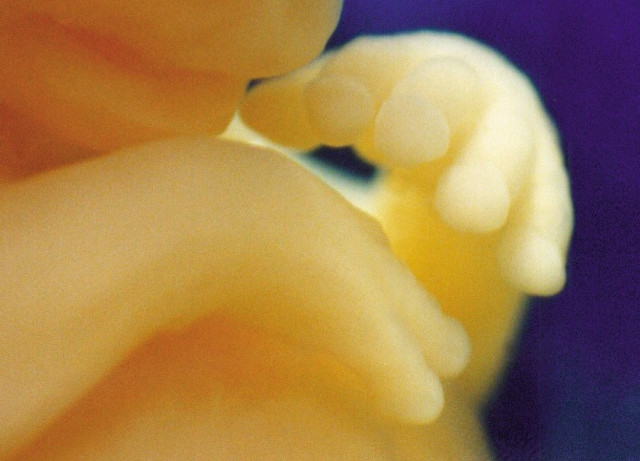

W 23. i 24. tygodniu życia dziecko zaczyna widzieć i śnić swoje pierwsze sny.

W 25. tygodniu życia Twojego dziecka możesz zauważyć indywidualne cechy jego osobowości.

Twoje dziecko mierzy już 34 cm, a jego waga wynosi 950 g. Badania wykazują, że możliwa jest komunikacja

W 14. tygodniu życia Twoje dziecko doświadcza eksplozji zmian. Ich tempo jest tak duże, że godziny liczą się tak jak lata.

Dziecko od momentu zapłodnienia pokonało w ekspresowym tempie

15. tydzień życia Twojego dziecka to intensywny rozwój jego mózgu. Dziecko świetnie się bawi w Twoim brzuchu, doskonaląc ruch. A Ty lada moment poczujesz

7 i 8. tydzień życia dla to czas, kiedy wszystkie narządy Twojego dziecka już powstały i zaczynają pracować. Na kolejnych etapach rozwoju będą doskonalone, ale już teraz maleńki